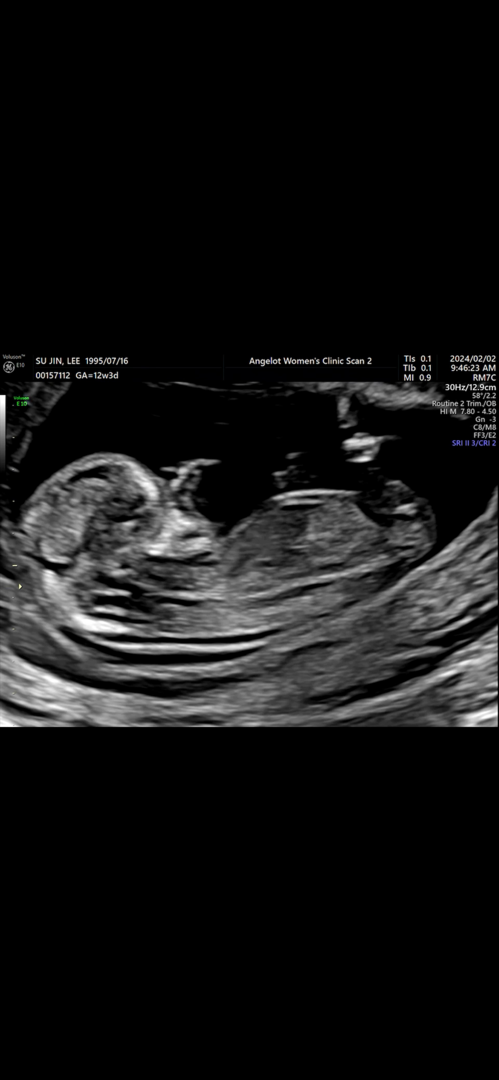

아내랑 내기했어요 각도법 봐주세요 ㅎ

아들인지 딸인지 의견 부탁드려요~

공주👸 같아요~

딸용

딸 같아용~